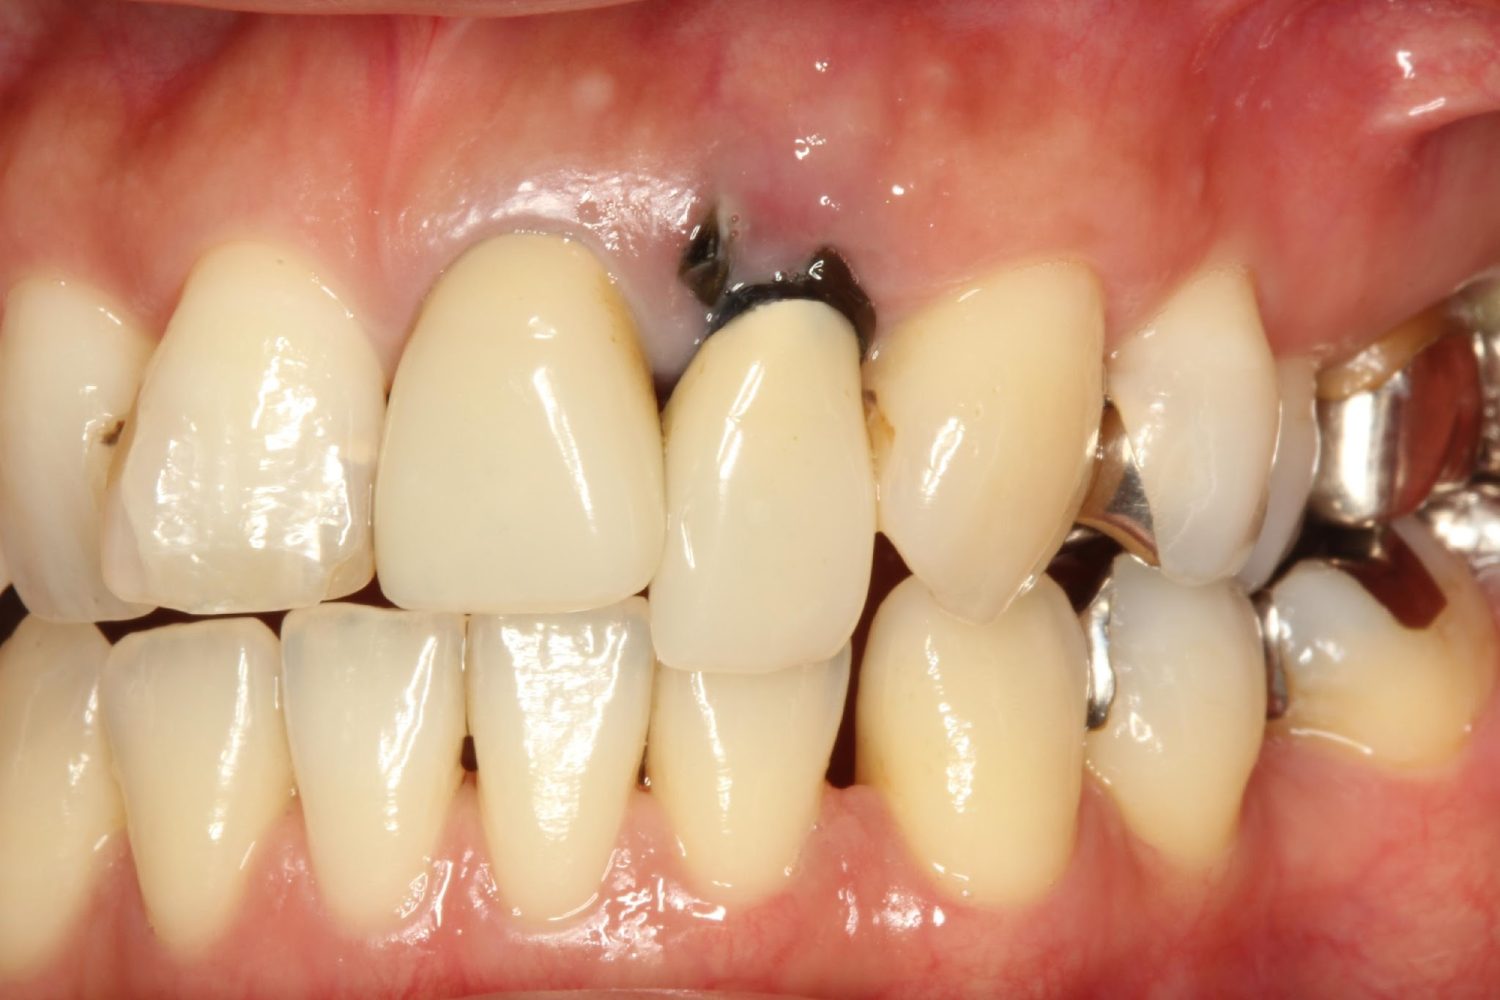

インプラント治療の症例紹介②

Before

After

主訴

前歯の脱落、歯肉の腫れ

治療内容

修復物の脱落時に支台築造のポスト部で歯質を破折。抜歯即時インプラント埋入をおこなったケース。

治療費

473,000 円(税込)

治療期間

8か月

治療回数

12回

想定されたリスク

※経年的な歯肉退縮の恐れ、インプラント周囲炎の恐れがありました。

残存した歯根に感染が少なく、抜歯時即時にインプラント埋入手術を行った。術後〇年経過し安定している状態。